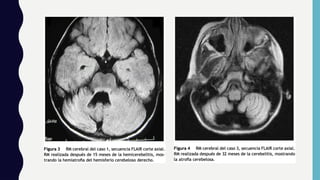

Diagnostico

• Neuroimagen

• LCR

• Laboratorio